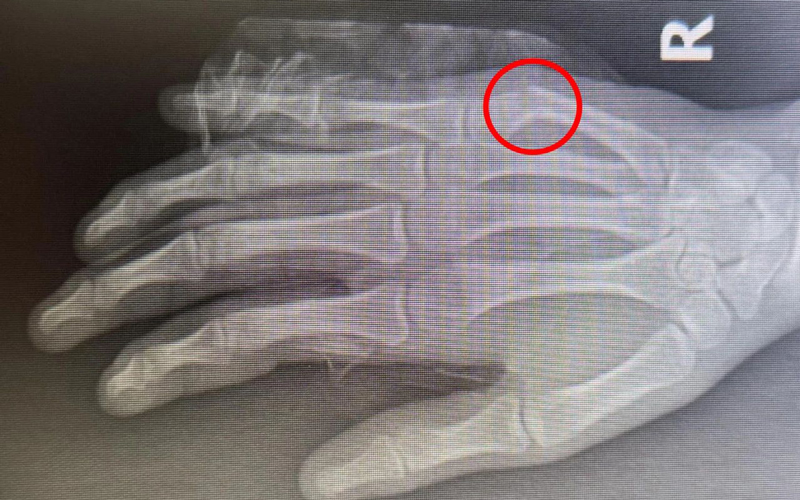

患者小徐今年16岁,因在学校不慎撞伤导致右手肿痛难忍来院就诊,穆中杰教授与科室医生认真研判病情,考虑患者为掌骨骨折可能,经过检查显示右手第5掌骨颈骨折,又称“拳击手骨折”,是临床上比较常见的手部骨折。

同患者及其家属进行沟通,决定行手法复位+杉树皮夹板固定,同时使用金黄散外用消肿止痛治疗,复位后骨折基本达解剖复位,患者及家属十分满意。

遂再次就诊于我院,经穆教授手法复位后,检查显示骨折复位良好。